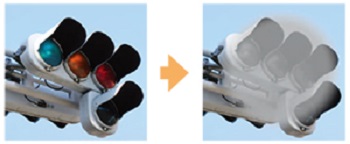

抗VEGF薬治療(硝子体内注射)とはどのような治療?

抗VEGF薬治療は、「導入期」と「維持期」に分けられます。 また治療期間は一貫して、月に1度の検査が必要になります。視力検査と眼底検査、必要に応じて光干渉断層撮影等を実施します。

抗VEGF薬治療は、「導入期」と「維持期」に分けられます。 また治療期間は一貫して、月に1度の検査が必要になります。視力検査と眼底検査、必要に応じて光干渉断層撮影等を実施します。

導入期

まず月に1回、抗VEGF治療薬を白目部分から硝子体へと注射します。これを3回、3ヵ月にわたって継続します。

維持期

1ヵ月に1回、眼の状態を観察・検査しながら、必要に応じて抗VEGF治療薬を同様に注射します。

「VEGF(血管内皮増殖因子)」は、血管からの血液や

その成分の漏出、新生血管の増殖の原因となっている分子です。抗VEGF治療薬の注射によって、VEGFの働きを抑制することができます。